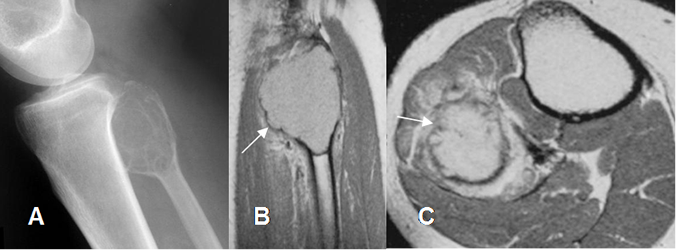

Fig 122. Tumor de células gigantes.

A: Rx lateral, B: RM coronal en T1 y C: RM sagital en T2. Lesión metafisiaria hipointensa en T1 e hiperintensa en T2, que rompe la cortical y forma una seudocápsula hipointensa en ambas secuencias.

Fig 123. Tumor de células gigantes.

A: Rx lateral. Lesión expansiva y sin ruptura de la cortical, en la cabeza del peroné.

B: RM sagital y C: RM axial en T1 con contraste. Formación de seudocápsula y gran realce del contraste.